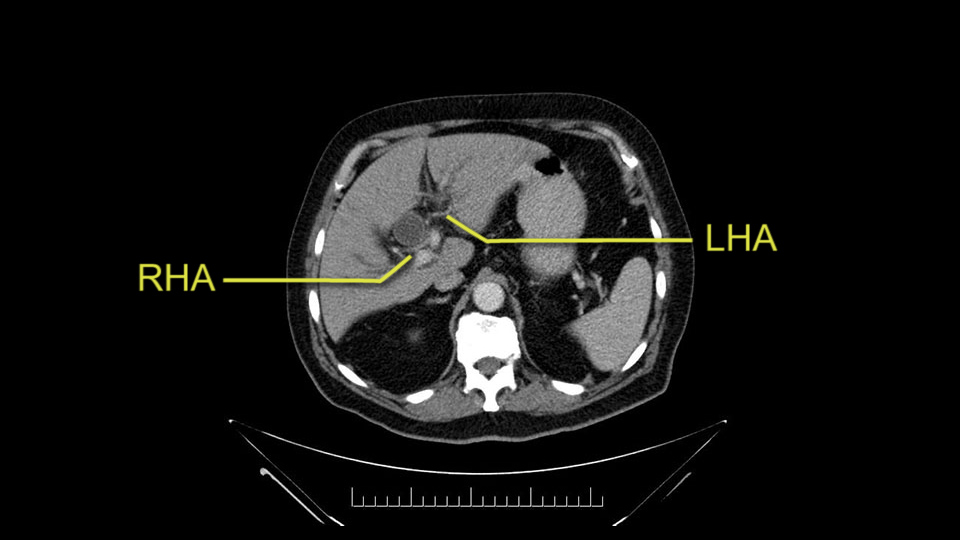

He has normal arterial anatomy: no accessory or replaced right hepatic artery, which is important because sometimes the right hepatic artery can come behind the neck of the pancreas and you have to be careful of that in a Whipple dissection.

Then you look for anomalies. The one you worry about the most doing a Whipple is a replaced or aberrant right hepatic artery coming off the SMA at its origin. So again, find the SMA. You can find it because the renal vein goes through it. Follow it up, up-up-up. Nothing coming off of there that I can see here. Nothing coming off of it, nothing coming off of it and just to confirm it, look at the celiac trfurcation. There’s the celiac, there’s the bifurcation, there's the splenic artery, hepatic artery. Make sure there’s a right, which there is here. The right usually goes under the bile duct: important when you’re going around the bile duct to do a Whipple. A replaced right goes under the portal vein and the bile duct way over here on the right. That’s about it.

The other slowing down moment would be the gastroduodenal artery. Confirming that the gastroduodenal artery is not a dominant artery supplying blood to the liver. Liver failure is something which we don’t want due to altered blood supply to the liver or hampered arterial blood supply to the liver. So I would dissect out the hepatic artery, the left and right branches very clearly. Put a bulldog clamp on the gastroduodenal artery, make sure that the perfusion of the liver is excellent on the right and left side, and then divide the gastroduodenal artery. I would avoid using crushing instruments or crushing clamps on the gastroduodenal artery because they have a tendency to shatter in patients who are old with friable vessels so you have to be careful and tackle it with the help of a 5-0 or a 6-0 prolene sutures. In younger patients, I would just apply clips and move on when it comes to dividing the gastroduodenal artery.

The second point about the vascular anatomy-, is to again look for right hepatic arteries in the hilum, coming from the superior mesenteric artery by palpating-through the Winslow Hiatus. Usually we will check for a pulse in the posterior aspect of the hepatic hilum, where a right hepatic artery should not usually be found. In this case, the precaution is to avoid an accidental ligation of the right hepatic artery that might jeopardize perfusion of the right lobe, or if there is a completely replaced hepatic artery that can put the liver circulation at risk.

I am a believer in pylorus preservation. And in this case I see no reason why that wouldn't be possible. Mobilize the duodenum, divide the gastroepiploic vessels and divide the duodenum. I try to divide it with a linear stapler about four centimeters from the pylorus to have adequate length for my GI anastomosis. This facilitates exposure of the head neck of the pancreas. I find the gastroduodenal artery. This patient has normal arterial anatomy. Always on every preoperative CT scan I look to see if there is a replaced right hepatic. In this case I did not see one. Regardless of how confident I am I always look carefully for variant anatomy. I always do a clamp test on the GDA before ligation. I doubly ligate the GDA with not just a tie but a suture ligature because of the risk of GDA blowout in patients with a leak.